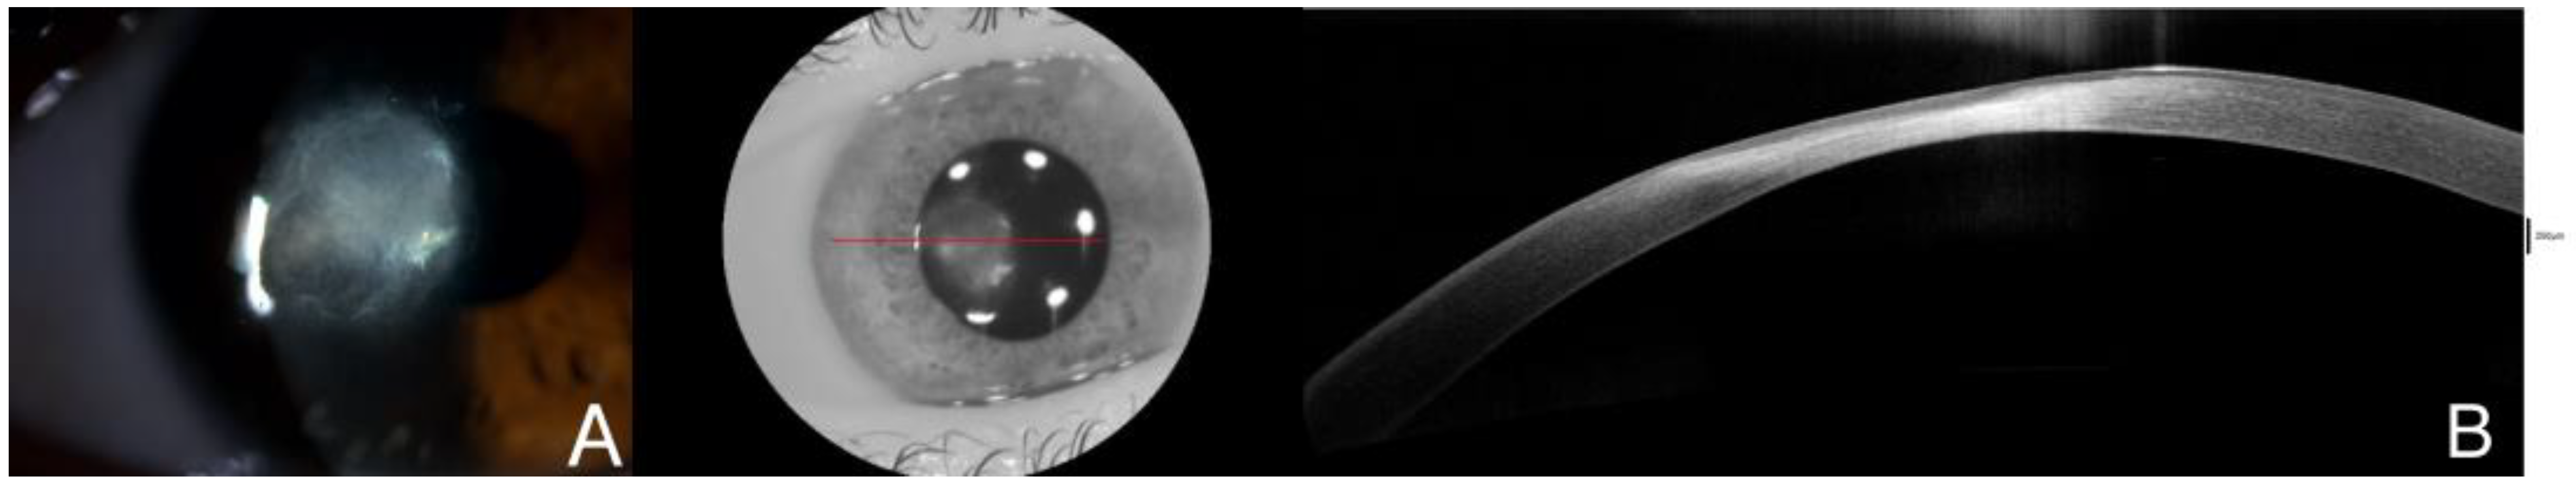

Slit-lamp examination demonstrates a 3 × 3 mm paracentral ulcer affecting epithelium and anterior stroma with 2 mm perilesional infiltrate. No signs of inflammation were identified on the anterior chamber (A). Initially, AS-OCT displayed Bowman layer disruption with stromal and epithelial edema, along with stromal hyperreflectivity, which may indicate an inflammatory process taking place (B). A corneal scrapping sample for microbiologic cultures was obtained and the patient started receiving hourly fortified topical treatment with Vancomycin and ceftazidime, along with topical voriconazole every two hours and ciprofloxacin ointment once a day. The best corrected visual acuity in that moment was 0.6 in the right eye. The red line is correspondene of the en face picture with the selected section on the AS-OCT.